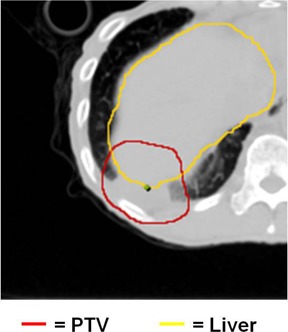

Lung tumors treated by SBRT can be generally categorized in two groups: “island” type tumors ((Fig. 1a) which are completely surrounded by lung parenchyma, and lung wall (LW)‐seated tumors ((Fig. 1b), in which one side of the tumor is adjacent to the interface between the lung and the surrounding anatomical structures. When irradiated, island‐type tumors will feature a lower‐dose shell (or ring, in a single CT slice) surrounding a higher‐dose core ((Fig. 2a). In contrast, LW‐seated tumors will feature a partial low‐dose shell or ring along the lung embedded portion of the tumor and a more isotropic dose distribution towards the lung wall side which abuts more similar density tissues ((Fig. 2b). In the SBRT lung treatment planning of either case, it is of pivotal importance to ensure that the tumor/lung interface region is not underdosed.

Figure 1. A CT slice image (a) of an island‐type lung tumor, which features the high‐density tumor completely surrounded by lower‐density lung parenchyma. A CT slice image (b) of a lung wall‐seated tumor in which the tumor abuts the chest wall and resides near lung‐adjacent OARs, such as the rib in this image.